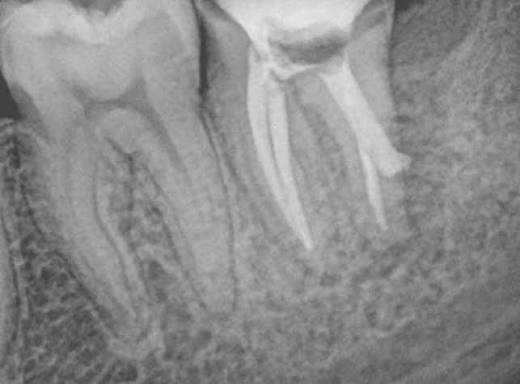

1. What Condition can be seen in this X ray regarding the tooth # 1.1.?